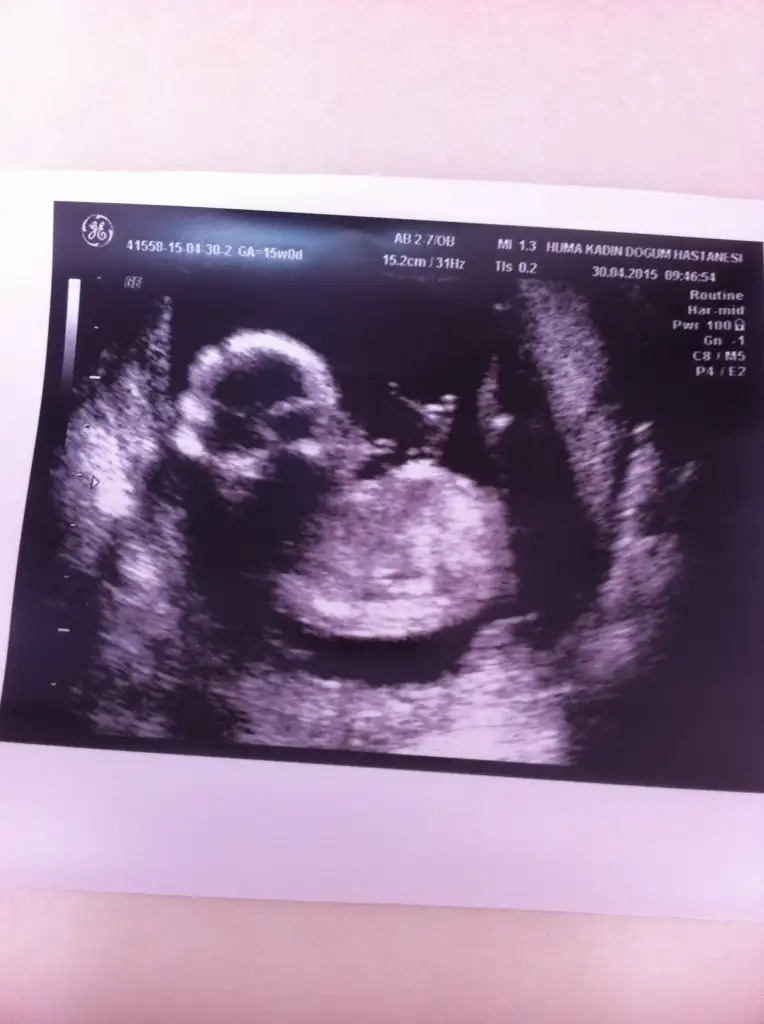

mrb arkadaşlar bugün 15 haftalık olduk kontrol vardı ve cinsiyetimize %51 den yüksek erkek dedi. resimler kalitesiz diyende var siz anlayabilirmisiniz merak beni öldürecek :)